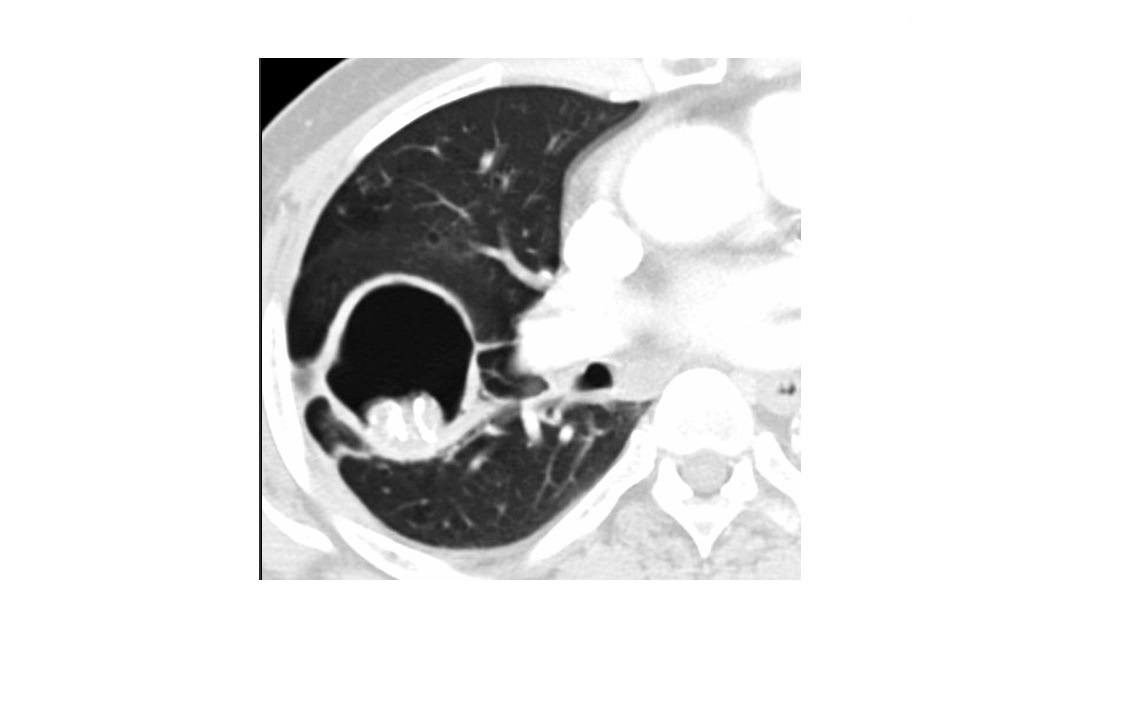

Birt-hogg-dube

Bilateral basilar predominant lentiform cysts abutting pleura, septa, and pulmonary vessels

Liver and skin lesions

Bilateral Renal oncocytomas

+ **chromophobe RCC